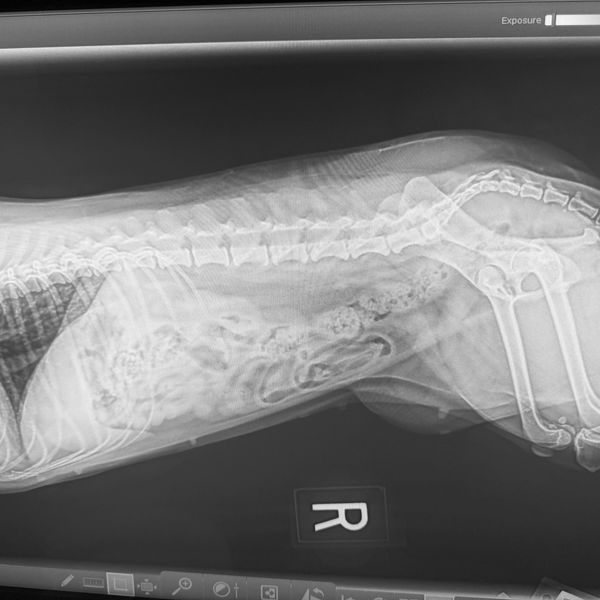

KSK Veterinary Services, LLC

Your Trusted Partner in Veterinary Relief